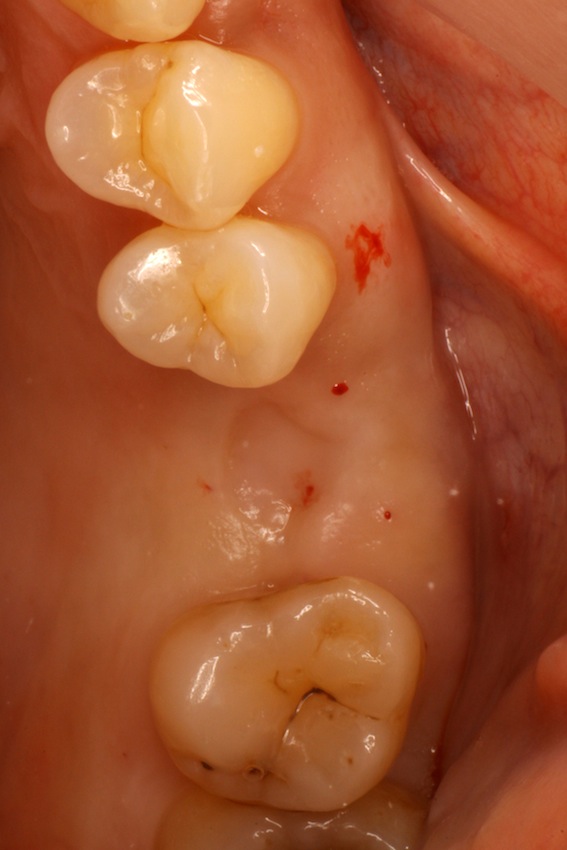

本日は症例提示を行います。

皆さん、歯がなくなった場合どのように治療すると思いますか?

ブリッジ、入れ歯、インプラントでしょうか?

それぞれの治療には利点、欠点が存在し、患者さんの希望、お口